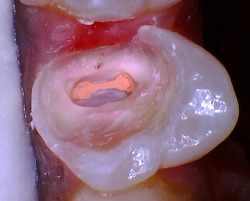

Here are some photos of what your teeth look like after a root canal procedure:

You can tell if a tooth had a root canal because you can see the root canal filling material inside of the tooth. This filling material is pink in color and easily distinguishable.

A commonality which is shared among all three of these after root canal treatment photos is that they are all missing a large chunk of tooth structure. The edges of the teeth also tend to be sharp as well. Consequently, you cannot place a crown on teeth that look like this. They will require a core buildup prior to making the crown.